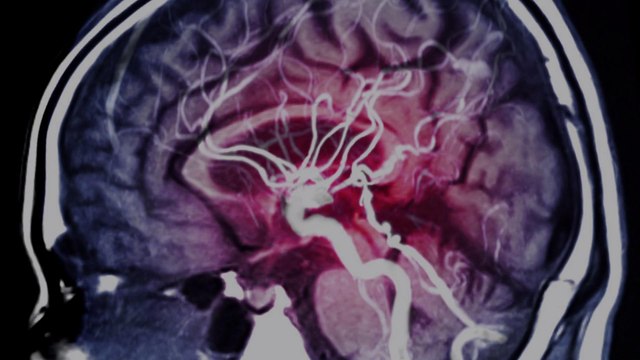

They aren't the same type of blood clot, nor do they require the same treatment—but experts say a slight comparison may help people understand that all medications come with risk.